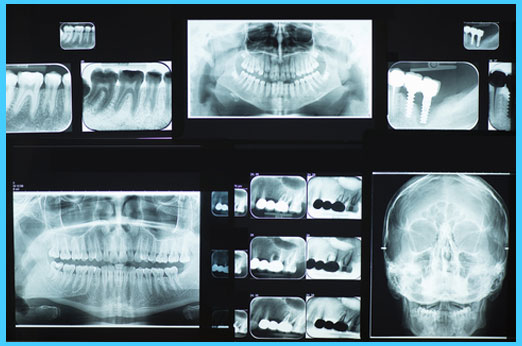

At Premier Dental Care, all of our x-rays are digital, even the panoramic x-ray machine.

Our x-ray system is a computerized imaging system that utilizes an electronic sensor instead of X-ray film. The sensors produce sharp and clear images that appear almost instantly on a computer screen.

Digital x-rays use up to 90% less radiation than conventional film X-rays and therefore, the concern for radiation exposure has been almost completely eliminated.